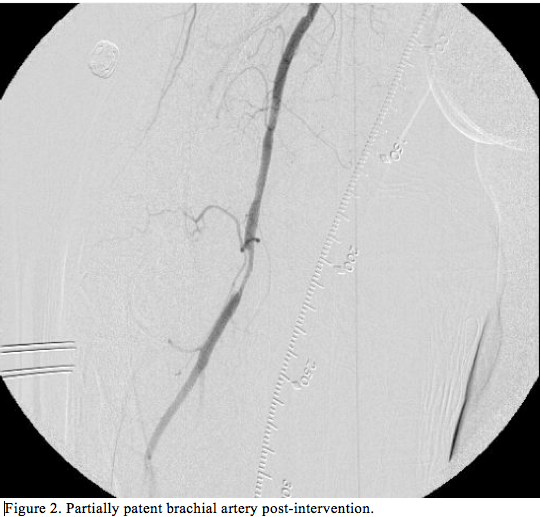

The next morning, the patient developed severe pain and discoloration of her right upper extremity. Physical examination revealed diminished right brachial and absent radial pulses. Emergency catheterization was performed through right common femoral artery, and showed 100% occlusion of the right brachial artery. We crossed the lesion with a 0.014˝ wire and performed multiple angioplasties with a 2.5 x 120 mm balloon at 4 atm. We delivered 8 mg of tPA through a 4 Fr Glide catheter (Terumo) with repeated angioplasties through a 2.5 x 20 mm balloon at 8 atm with lesion reduction from 100% to less than 20% and TIMI flow improvement from 0 preintervention to 3 postintervention. Postprocedure, the patient was kept on heparin infusion for 24 hours. She was discharged the following day on dual-

antiplatelet therapy (aspirin 325 mg once daily and clopidogrel 75 mg once daily). Repeat Doppler ultrasound at 6 months showed patent brachial artery.